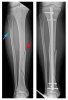

Ngô Hoàng Thịnh: ‘Hùng Dũng gãy chân đau 1 thì tôi đớn đau 10’